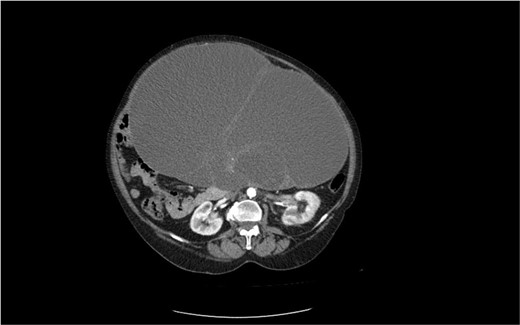

The second case is of a 62-year-old woman, admitted to a surgery clinic with abdominal distention, difficult defecation, and ultrasound data of a large tumor in the abdomen. CT describes a large tumor formation, reaching ventrally to the anterior abdominal wall, measuring 317/202/272 mm/d with a predominantly cystic structure (Fig. 3). The finding has a homogeneous content and multiple intralesional septa with a mass effect in relation to small intestine, main abdominal vessels, compress and dislocates the transvers colon and stomach. Operative treatment followed with laparotomy and evacuation of about 8 l of serous fluid from the cystic formation described on CT. Given the concerns about the presence of malignancy, a hysterectomy with adnexectomy and appendectomy was performed. Histopathologically, a multilocular mucinous cystadenoma of the left ovary was proven. The uterus has cystic endometrium and myometrium with intramural leiomyomas and adenomyosis, and the appendix with fibrinous-purulent periappendicitis. The patient recovered and was discharged on the seventh postoperative day without complications.

CT image of a large ovarian mucinous cystadenoma of the left ovary.